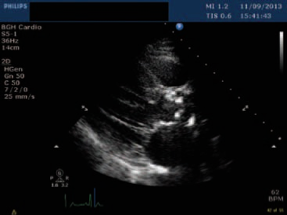

First-line: non-invasive gold standard:

-

Echocardiography and Doppler: A narrow AV is diagnostic; mean pressure gradient and jet velocity across the valve.

Calcification and narrowing of the AV. Increased mean aortic pressure gradient and transvalvular velocity. Signs of cardiac remodeling, e.g., concentric hypertrophy.

Calcification and narrowing of the AV. Increased mean aortic pressure gradient and transvalvular velocity. Signs of cardiac remodeling, e.g., concentric hypertrophy.